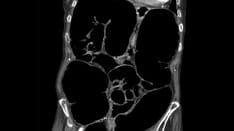

Functional constipation is common in children and adolescents. Symptoms include infrequent bowel movements with hard stools that can be difficult or painful to pass.

• Presence of a large fecal mass in the rectum